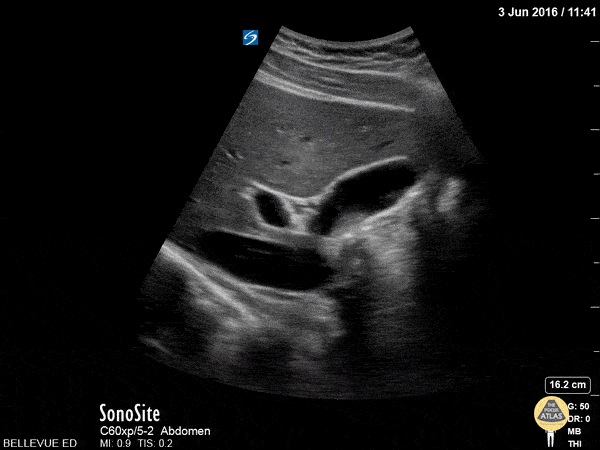

In this clip we see the liver on the left, and the IVC inferior to the liver with a hepatic vein draining into it. The ovoid anechoic gallbladder is in long axis in the center of the screen. To the left of the gallbladder we see the portal vein in cross-section. Running just superior to the portal vein, in long axis, is the narrow common bile duct. Hannah Kopinksi and Dr. Lindsay Davis - NYU Emergency Medicine